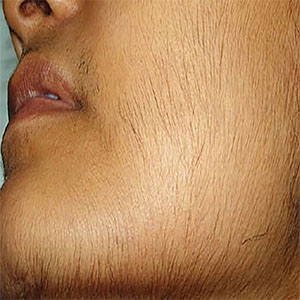

ارزیابی و درمان هیرسوتیسم

ارزیابی و درمان هیرسوتیسم هیرسوتیسم یک وضعیت است که در آن زنان تولید بیش از حد موی بدن…